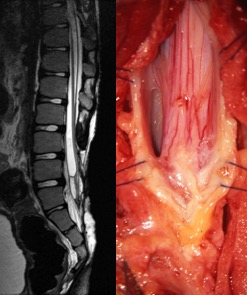

l’IRM montre un aspect compatible, elle permet rarement d’affirmer le syndrome de

moelle attachée. Elle retrouve parfois un kyste dermoïde d’inclusion (fragment d’épiderme inclus lors de la fermeture initiale) ou une syringomyélie (qui doit faire vérifier le fonctionnement de la valve avant d’opérer la moelle).

traitement

il est chirurgical. la défixation peut être délicate, plus pour les myélolipomes que pour les myéloméningocèles. les risques opératoires sont :